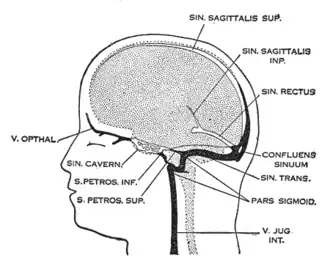

The meningeal lymphatic system is composed of a network of vessels along the dural sinus in the dura which express lymphatic endothelial cell marker proteins, including PROX1, LYVE1, and PDPN. The vessels extend along the length of both the superior sagittal and transverse sinuses and directly connects to the deep cervical lymph nodes.[1] These meningeal lymphatic vessels drain down and exit the skull along the dural venous sinuses and meningeal arteries. Meningeal lymphatic vessels also drain out of the skull alongside cranial nerves and through the cribriform plate. Molecular profiling indicates that the vessels are conventional lymphatic vessels: they express high levels of PROX1, LYVE1, PDPN and VEGFR3, but low levels of PECAM1. Meningeal lymphatic vessels absorb cerebrospinal fluid and drain into the deep cervical lymph nodes.[2]

Several unique attributes differentiate meningeal lymphatic vessels from lymphatic vessels in peripheral organs. Compared to peripheral lymphatic vessels, the meningeal lymphatic network is markedly less complex, with far less tissue coverage and lymphatic branching. Furthermore, meningeal lymphatic vessels are generally smaller than those in the periphery and display a structural homogeneity along the dural sinuses, remaining thinner and mostly unbranched along the superior sagittal sinus while growing larger and more branched along the transverse sinuses.[1] The meningeal lymphatic vessels are also unique for their scarcity of valves, which prevent back-flow of lymph. While the vessels in the superior parts of the skull were mostly devoid of valves, the larger lymphatic vessels of the basal parts only contain scattered valves.[2]